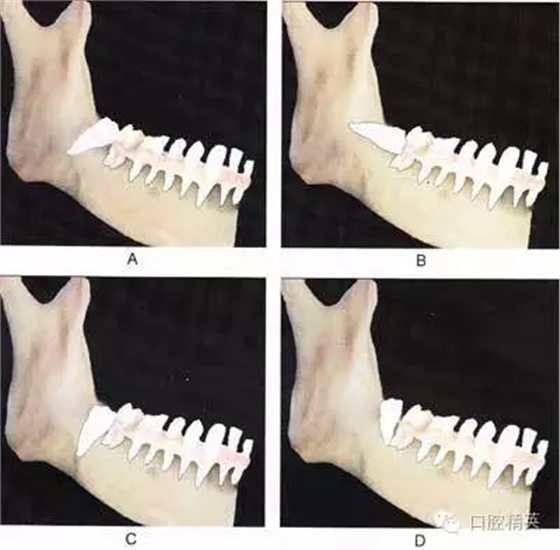

圖⒍1 根據(jù)第三磨牙牙體長(zhǎng)軸與第二磨牙牙體長(zhǎng)軸所成的角度不同可分為:近中 阻生(圖A):第三磨牙牙冠向近中傾斜;水平阻生(圖B):第三磨牙與第二磨牙牙體長(zhǎng)軸相互垂直;垂直阻生(圖C):第三磨牙牙體長(zhǎng)軸與第二磨牙平行;遠(yuǎn) 中阻生(圖D):第三磨牙牙冠向遠(yuǎn)中傾斜